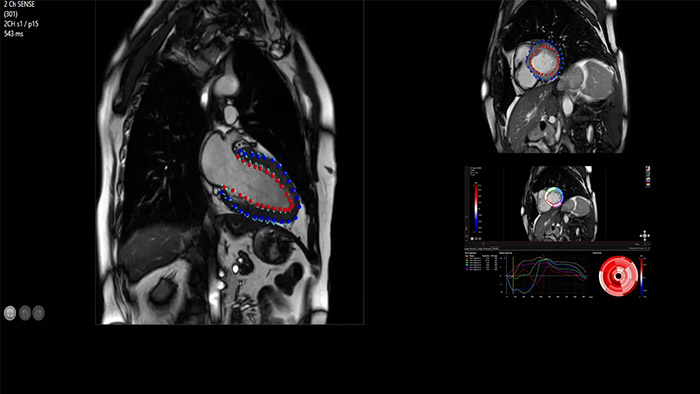

O IntelliSpace Portal oferece um abrangente conjunto de RM cardíaca, fornecendo fluxos de trabalho dedicados para análise funcional, viabilidade, LGE, avaliação do mapeamento cardíaco e análise funcional do VD/VE em menos de 5 min. por caso3.

A utilidade do diagnóstico e prognóstico da RM cardíaca está a aumentar. Avalie a anatomia e função do coração utilizando aquisições cine, adquira informações sobre a perfusão e viabilidade do tecido cardíaco, visualize potenciais edemas com sequência de sangue escuro, aceda e quantifique mesmo a caracterização do tecido com a CardiacQuant.